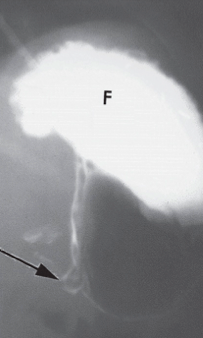

Meckel’s diverticulum

Cause: Congenital midgut disorder. Persistent remnant of vitelline duct

Features: